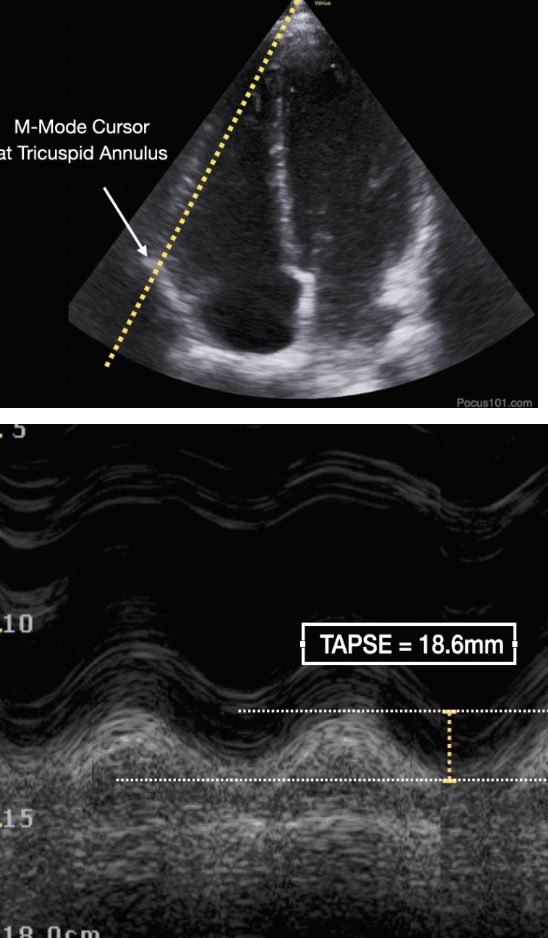

Now, let’s add some numbers to this and talk about TAPSE:

What does it stand for?

Tricuspid Annular Plane Systolic Excursion

What is it?

• It is an assessment of the global systolic RV function.

• It measures the distance that the RV annular segment moves longitudinally during contraction.This correlates with RV ejection fraction since the RV does not contract concentrically like the LV does.

How to find TAPSE?

1. Obtain Apical 4 Chamber view, making sure you are able to completely see the right ventricle.

2. Turn on M-Mode and place the cursor at the tricuspid annulus.

3. Measure the distance from peak to trough, which represents the distance the annulus moves from its end-diastolic position to its maximum systolic position.

How do you interpret TAPSE?

• If TAPSE is greater than 16mm, that indicates normal right ventricular function.

• If TAPSE is less than 16mm, it suggests there is right ventricular systolic dysfunction. This can be seen in the setting of PE as well as chronic processes such as pulmonary hypertension, right ventricular MI, etc.